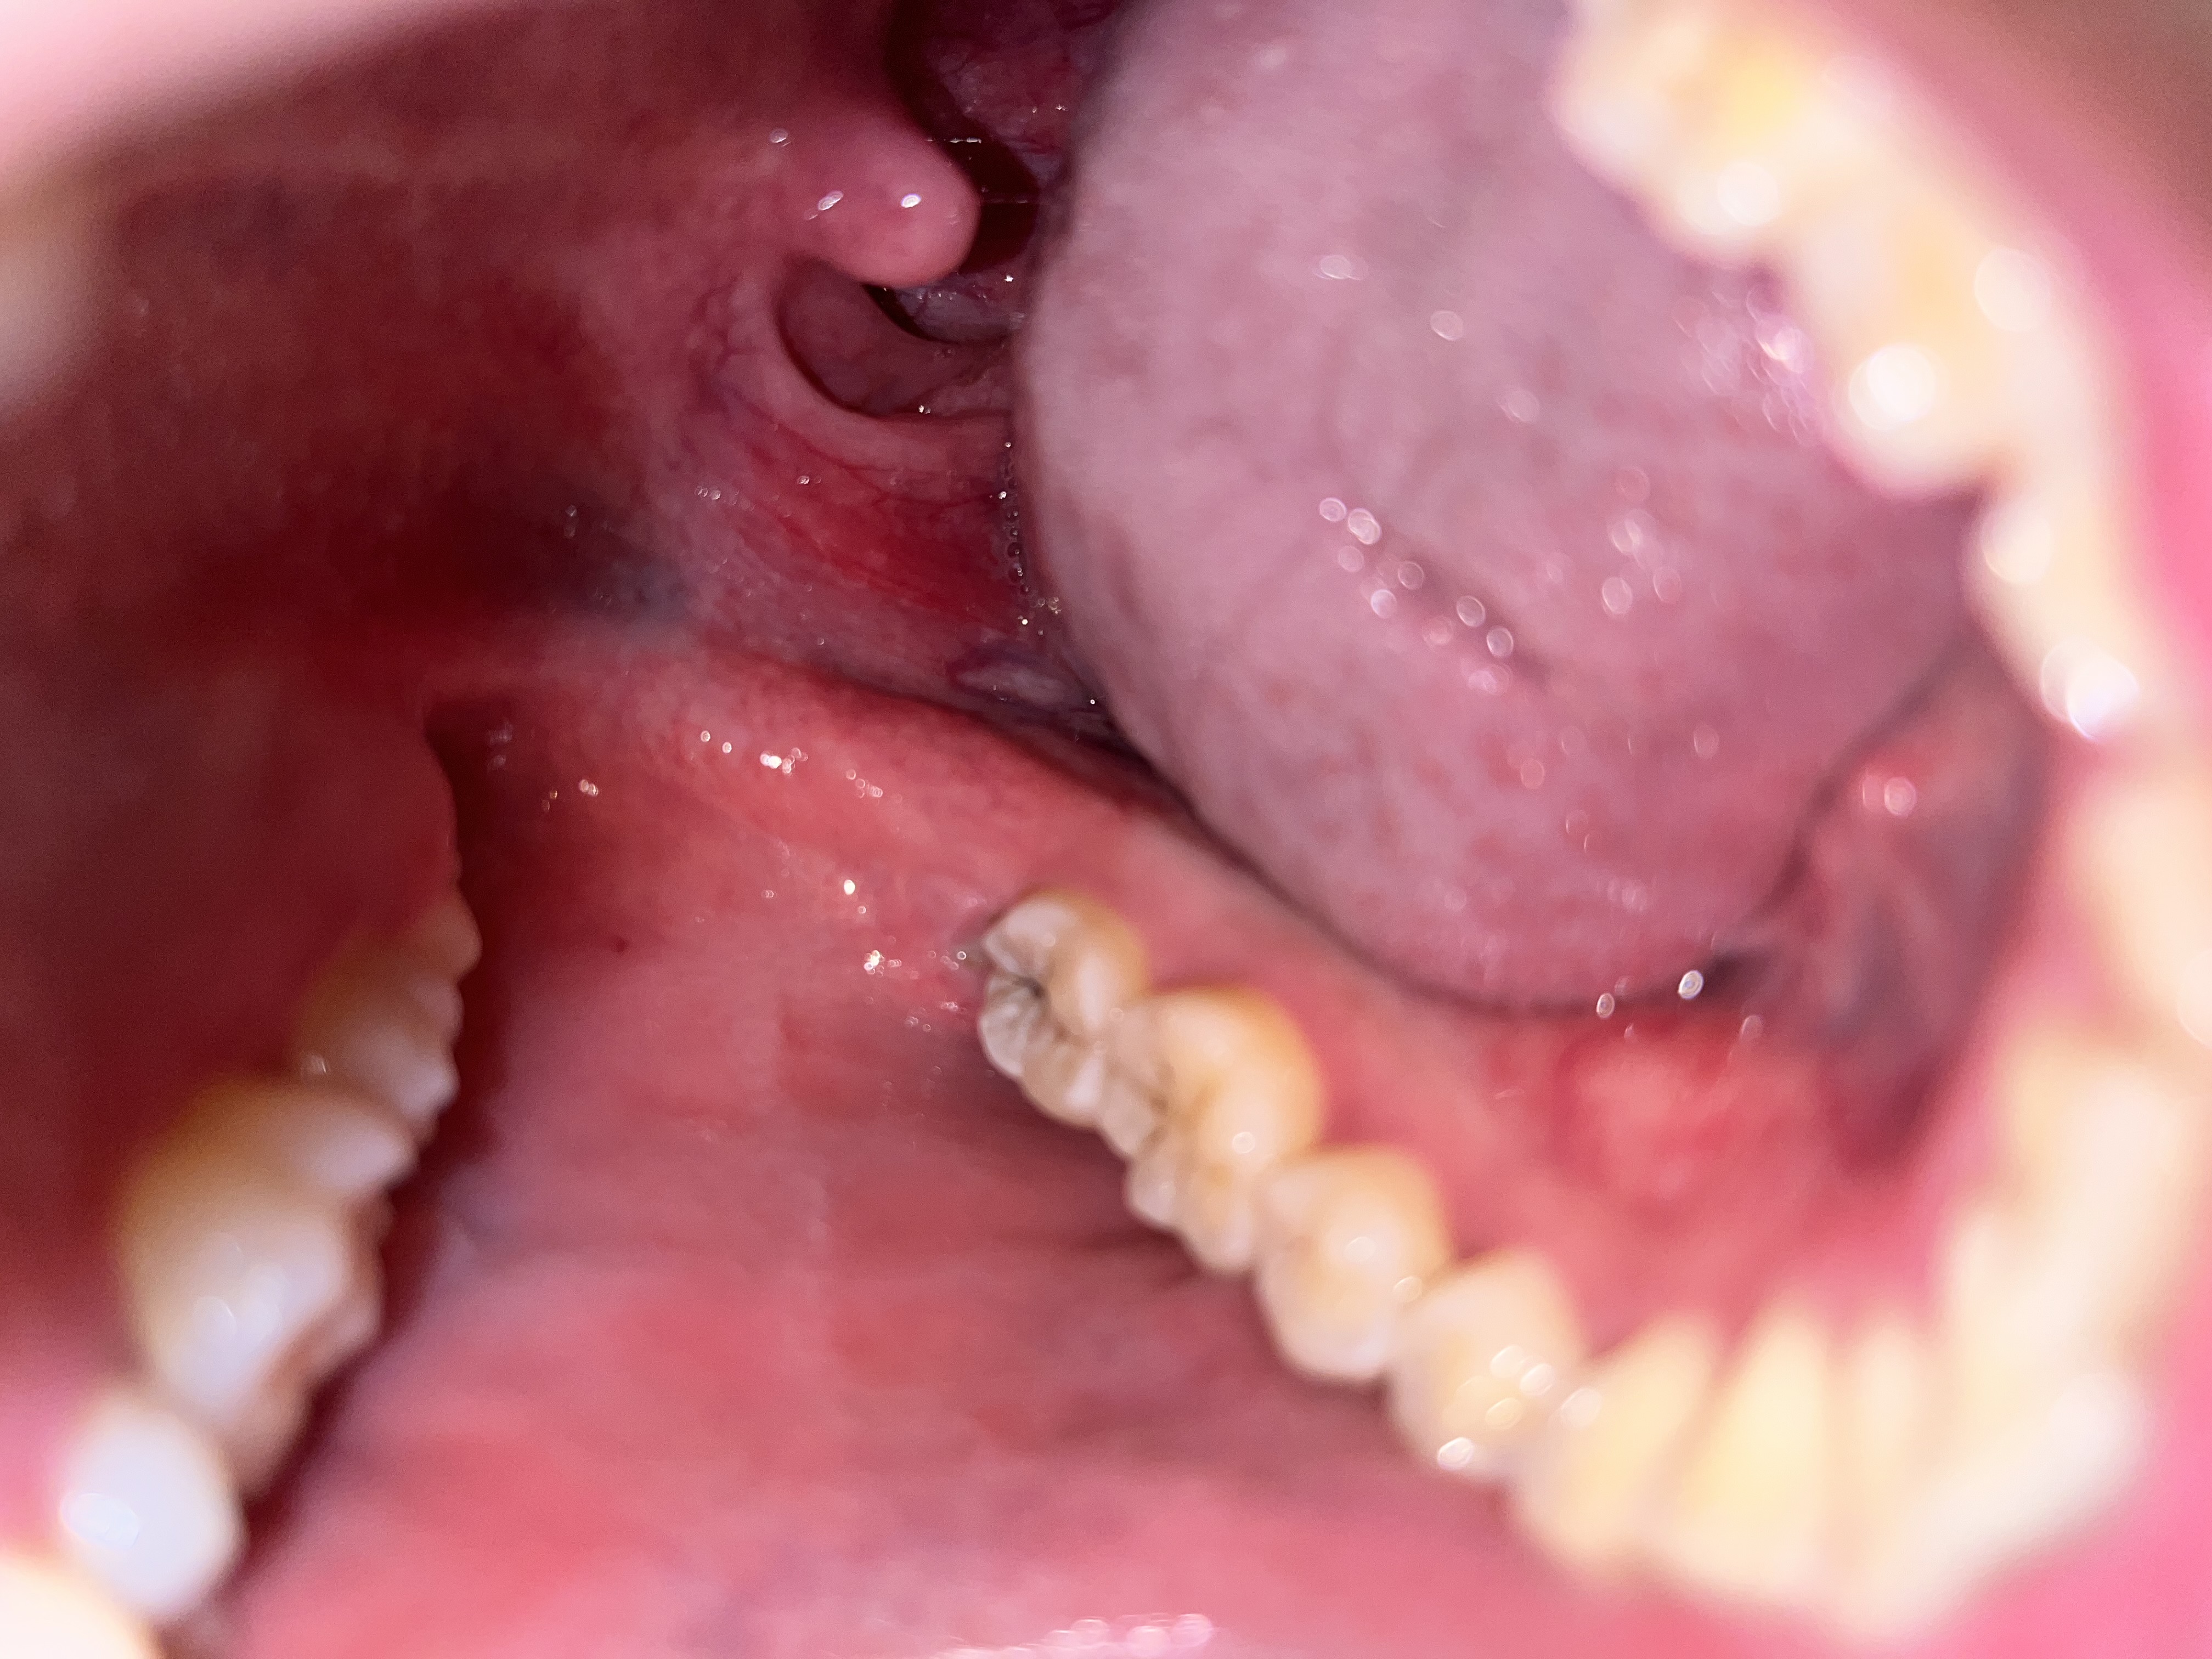

อยากทราบว่าสีขาวๆ คืออะไรหรอครับ และอันที่วงๆ ก่อนหน้านี้มีเจ็บคอเป็นๆ หายๆ บ่อย เคยเป็นกรดไหลย้อนนานแล้ว  กับภูมิแพ้ ผมสงสัยว่าสีขาวๆ คืออะไร ที่วง และกับอีกอันทอนซิลข้างขวาบวมหรือปล่าวครับ (แลบลิ้นเห็นชัดขึ้นอยู่ข้างขวา) กังวลมากครับ ขอบคุณมากครับถ้าตอบอธิบายให้หายกังวล

ลักษณะเหมือนกับแผลร้อนในน่าจะหายภายในสองอาทิตย์ครับ ส่วนต่อมทอนซิลไม่ผิดปกติสองข้างโตไม่เท่ากันได้ครับ ไม่ต้องกังวลครับ นอนหลับให้สบาย